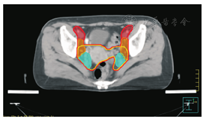

笔者所在科室对于FIGO临床分期为ⅡB期宫颈癌(阴道穹窿受侵、宫旁受侵近盆壁)的调强放疗流程及靶区CTV勾画范围建议如下。对其定位前准备工作包括:患者于定位前30~40 min排空膀胱,再饮水500 mL(含造影剂碘化醇10 mL),显影小肠。对其靶区CTV勾画具体操作步骤为:让患者取仰卧位,身下垫胸、腹平板,双手抱肘并上抬置于额头,热塑体膜固定(上腹至大腿上约1/3处);待热塑体膜冷却成形后,激光灯下于体前正中和两侧分别置铅点(尽可能靠近靶区中心)。此时尽可能行CT增强扫描,以更清楚显示解剖位置;对造影剂过敏、高龄、伴有严重并发症等不适合行CT增强扫描者,仅进行平扫。CT检查的扫描范围为:第一腰椎体上缘至坐骨结节下2 cm,层厚为5 mm,若腹主动脉旁淋巴结转移,则上移至隔顶;若全阴道浸润、腹股沟淋巴结转移,则下移至外阴下4 cm。其中,对靶区CTV勾画:放疗前,应常规实施CT、MRI或PET-CT检查,以明确肿瘤靶区范围及是否存在远处转移(部分远处转移病变,可与原发部位同时进行放疗)。对于其GTV勾画,则包括临床肉眼可见或可触及的,或可通过检查手段证实的肿瘤区域,具体包括宫颈肿瘤、受侵宫旁及阴道组织。MRI检查是确定软组织及宫旁受侵的较理想方法。若腹膜后淋巴结转移,需对淋巴结照射剂量进行加量时,CTV则应单独勾画转移淋巴结靶区。CTV勾画分为局部肿瘤区域和淋巴引流区域。局部肿瘤区域CTV勾画,包括局部肿瘤GTV及显微镜下可见的亚临床肿瘤病变,首先为宫颈、宫体、宫旁和阴道CTV勾画。①宫颈CTV:勾画全部宫颈。②宫体CTV:勾画全部宫体。③宫旁CTV:勾画上界为乙状结肠跨过子宫及输卵管处,下界为泌尿生殖膈,前界为膀胱后壁/髂外血管后缘。若子宫前倾明显,则子宫前界为宫旁前界,后界为宫骶韧带和直肠系膜前缘,内侧界为子宫颈阴道,外测界为骨盆壁,不包括肌肉和骨。值得注意的是:若宫骶韧带受累,CTV勾画则需将整个宫骶韧带全部包括在内,此时直肠系膜淋巴结及直肠周淋巴结均应包括在内。对于FIGO临床分期为ⅢB期及以上者,CTV应将直肠周淋巴结勾画在内,宫旁靶区与髂淋巴结及闭孔淋巴结区重叠。④阴道CTV:若阴道无受侵,则勾画阴道上段1/2,若上段受侵,则勾画阴道上段2/3,若阴道广泛浸润,则勾画全阴道。其次,盆腔淋巴结引流区包括宫颈旁、宫旁、闭孔、髂内、髂外、骶前及髂总淋巴结CTV勾画,依照其血管走行进行勾画。①髂总动脉CTV:上界为腹主动脉分叉下缘,下界为髂总动脉分叉下缘;前界为血管前7 mm,后界为血管后7 mm;内侧界为血管内侧7 mm,外侧界为血管外7 mm,腰大肌内侧缘,包括腰大肌与椎体旁间隙。②髂外动脉CTV:上界为髂总动脉分叉下缘,下界为股骨头上缘即股动脉;前界为血管前7 mm,后界为血管后7 mm;内侧界为血管内侧7 mm,以子宫、卵巢、肠管、输尿管及膀胱为界,外侧界为血管外7 mm,腰大肌及髂腰肌内侧缘。③髂内动脉CTV:紧邻髂内血管及其分支,上界为髂总动脉分叉下缘,下界为尾骨肌上缘、坐骨棘或子宫动静脉上端;前界为血管外7 mm,后界为上部以骶骨翼为准,中下部至梨状肌前缘或臀下动静脉;内侧界为血管外7 mm,外侧界为头侧髂腰肌、髂肌或骶髂关节外侧,中间为髂骨、髂腰肌或髂肌内侧缘;尾侧界为闭孔内肌或梨状肌内侧。④闭孔淋巴结CTV:上界为骶髂关节下缘连接至髂内淋巴结,下界为闭孔上缘;前界为上中部分连接到髂外,下部至耻骨后缘,后界上中部连接到髂内,下部至闭孔内肌后缘;内侧界至膀胱、子宫及肠管,沿骨盆壁向内扩18 mm,外侧界至闭孔内肌、髂肌、髂腰肌或髂骨。⑤骶前淋巴结CTV:上界为髂总分勾画范围,见图1,图2,图3,图4,图5,图6。